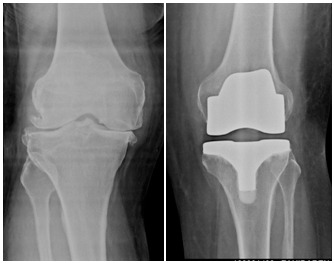

Total Knee Replacment

X-Ray before-after in knee replacement